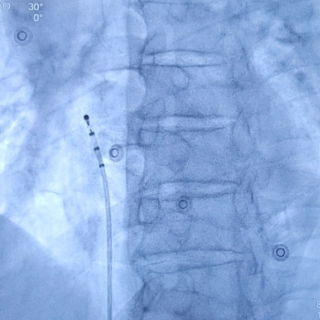

心房无导线起搏器最终植入位置

手术首先利用电生理四极导管标测Bachmann束区域,留影做参考;再次利用保护套筒造影精准确认植入位置,后退保护套筒,将心房无导线旋入1.5圈,参数良好且稳定。